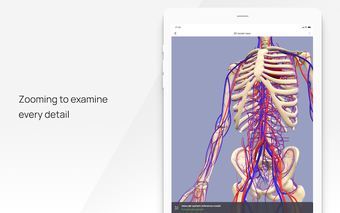

In this atlas of human pathologies you can learn about diseases, their causes, symptoms, and treatment. It contains all the essential information about the anatomy of the human body and its organs. You will be able to study diseases and their causes from an anatomy point of view. It contains information about diseases, their symptoms, and their treatment. In addition, you will be able to view 3D models of all the important organs of the human body.

All 3D pathology models are developed in close cooperation with medical experts of hospitals and research centers. They are thought out to the very smallest detail. Each category contains models of healthy organs.